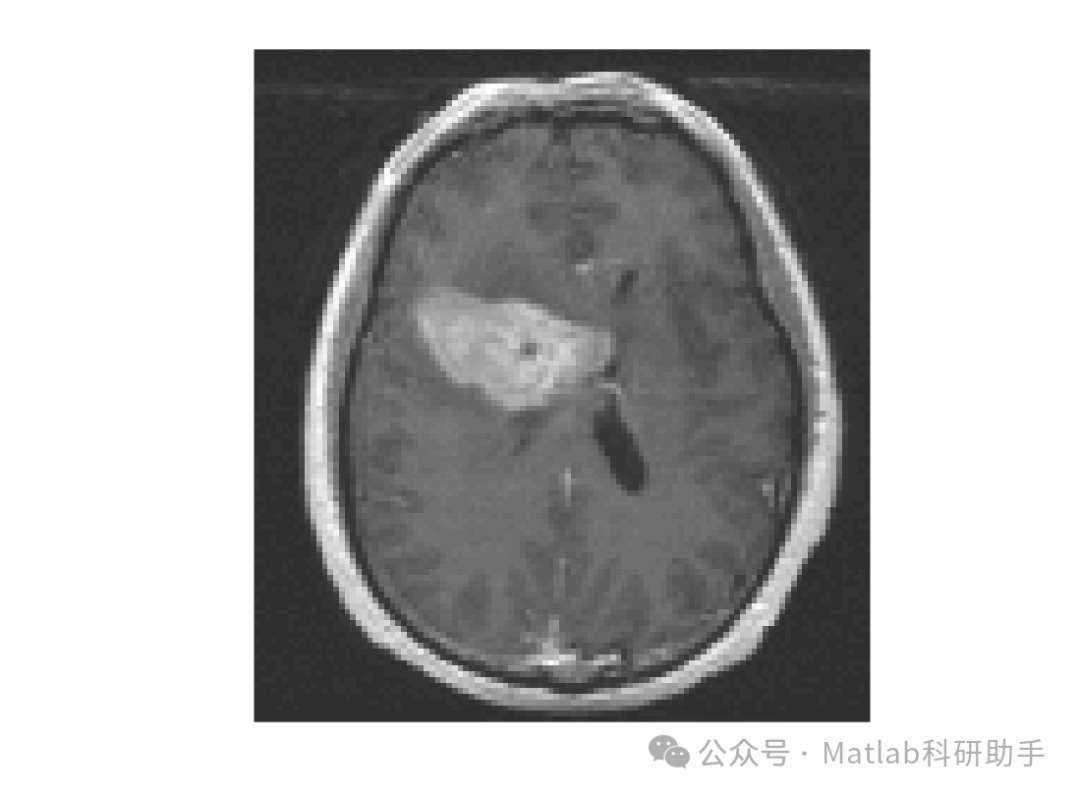

在医学图像分割领域,该模型展现出良好的性能 。以脑部 MRI 图像分割为例,由于脑部组织灰度不均匀,且肿瘤边界模糊,传统分割方法难以准确分割出肿瘤区域 。使用由局部高斯分布拟合能量驱动的活动轮廓模型,通过对 MRI 图像局部区域的高斯分布特性进行分析,能够有效区分肿瘤组织与正常组织 。在分割过程中,区域拟合能量项引导轮廓向肿瘤边界移动,正则化能量项保证轮廓的光滑性 。经过水平集函数的迭代演化,最终准确地分割出肿瘤区域,为医生的诊断和治疗提供了清晰的图像依据 。